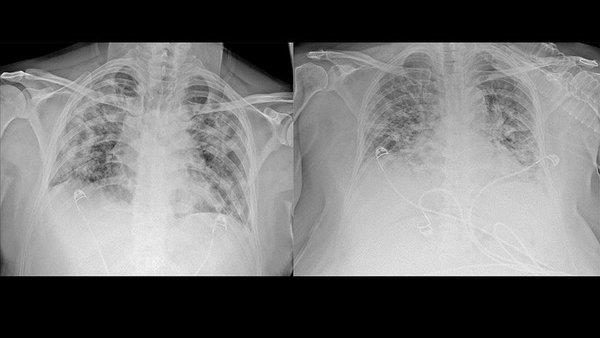

Dünya Sağlık Örgütü uzmanları, Covid-19 ile nikotin ilişkisini inceleyen araştırmaları gözden geçirdiklerini belirtti. Sigara içenlerde Covid-19 vakalarının daha ağır seyrettiğini söyleyen DSÖ yetkilileri Avrupa Hastalıkları Kontrol Merkezi'nin (ECDC) bildirisinde sigara içenlerin Covid-19'a karşı 'riskli gruptan' oldukları uyarısını da hatırlattı.